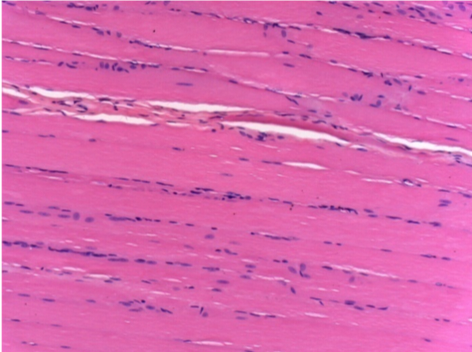

L:Pretibial-No treatment

10 days after Endopeel Injection 0.1ml in the right pretibial muscle.

Here you may see the formation of the vacuoles which are surrounded by lymphocytes. Vacuoles are different from tissue necrosis . The presence of lymphocytes is related to the permeability of the cell membranes.